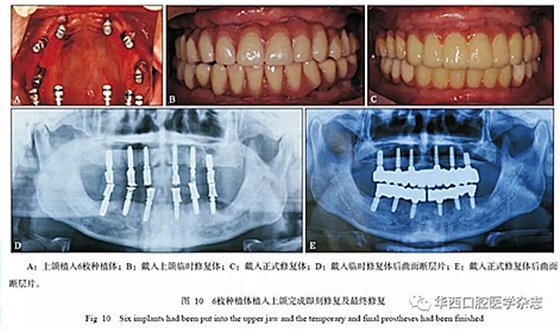

本病例最小唇側(cè)基托邊緣位于前牙區(qū)牙槽嵴的冠方,前牙區(qū)牙槽嵴寬度可以支撐口唇凸度,但齦緣位置距離牙槽嵴頂距離大于4 mm,不是單純的牙缺失,為MLTR-Ⅰ類(lèi)2亞類(lèi);與患者討論后決定采用復(fù)合式義齒修復(fù)。 采用微創(chuàng)技術(shù)進(jìn)行上下頜種植手術(shù)(圖10A),放置多基基臺(tái),制作臨時(shí)修復(fù)體(圖10B、D),待3個(gè)月種植體骨結(jié)合完成后,完成最終修復(fù)(圖10C、E和圖11)。